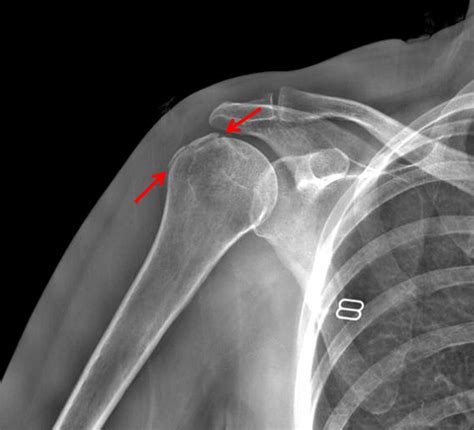

Clinical Significance and Common Injuries

Due to its exposed position and the intense forces placed upon it, the greater tubercle of humerus is susceptible to various pathologies. Understanding these conditions is vital for effective diagnosis and rehabilitation. One of the most common issues associated with this anatomical site is greater tubercle fracture, which often occurs during high-impact falls or contact sports.

Diagnostic Imaging and Rehabilitation

Diagnosing issues involving the greater tubercle of humerus typically involves a combination of physical examinations and imaging techniques. X-rays are the gold standard for identifying bony fractures, while MRI scans are essential for visualizing the soft tissues—specifically the rotator cuff tendons—that attach to the bone. Physicians look for irregularities in the bone surface, bone spurs (osteophytes), or evidence of tendon tearing near the insertion sites.